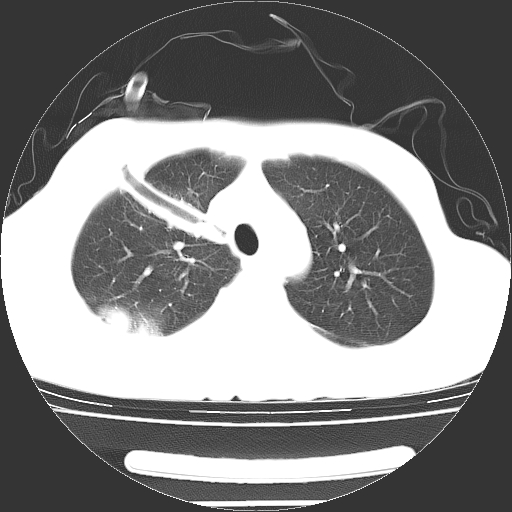

以下是引用dyqct在2008-4-29 8:43:00的发言:[br][br] 支持右侧胸腔包裹性积血。闭式引流管是不是插的太深了?

以下是引用zjzjr在2008-4-29 14:11:00的发言:[br]支持右侧胸腔包裹性积血。闭式引流管是不是插的太深了?胸腔引流,引流管快进入纵隔了.